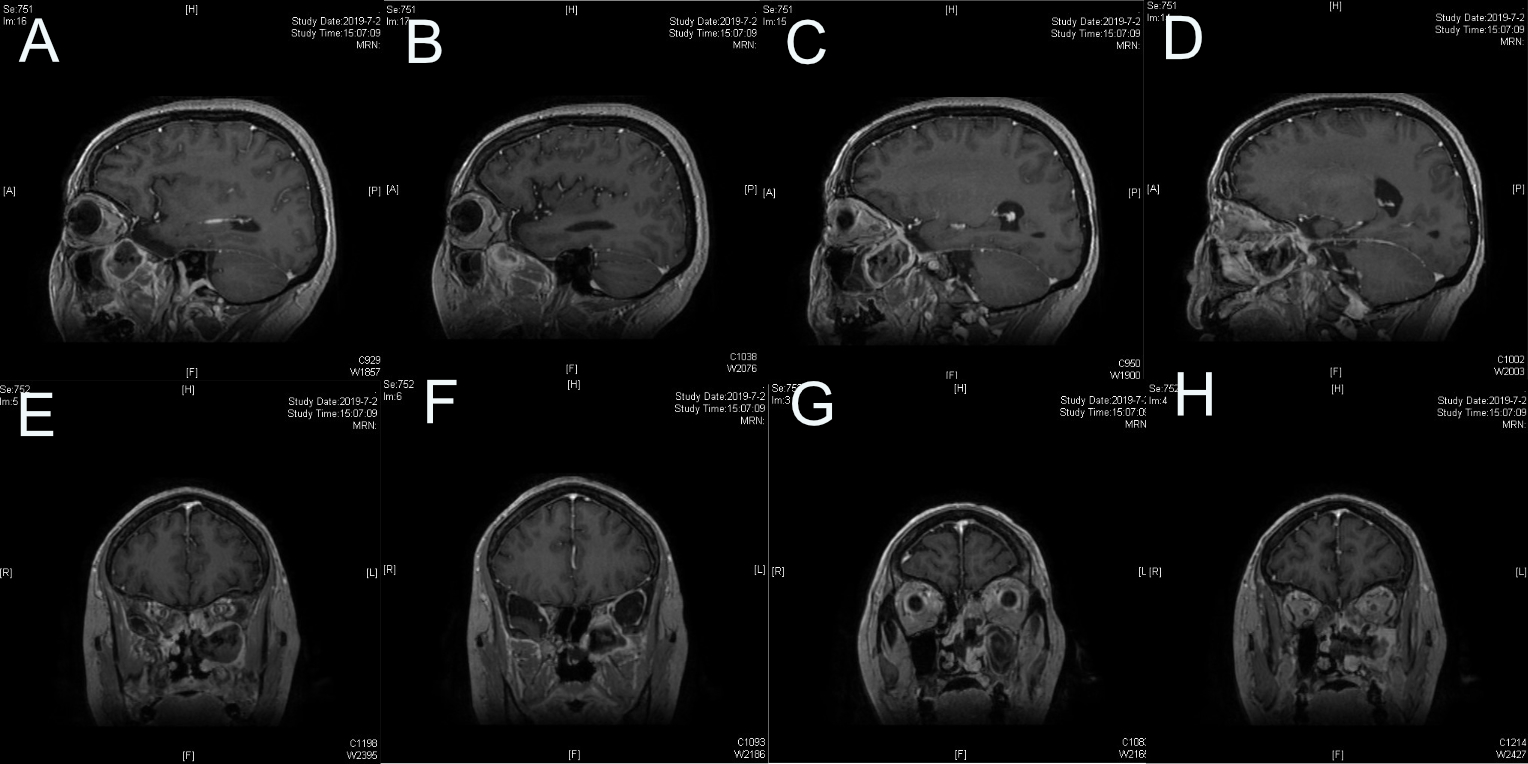

图10.肿瘤起源于中颅底圆孔,圆孔已明显扩大

图11.肿瘤完全切除

图12.术后CT左侧颅底术后改变,术区肿瘤完全切除。

图13.左侧颅底术后所见,肿瘤全切除。